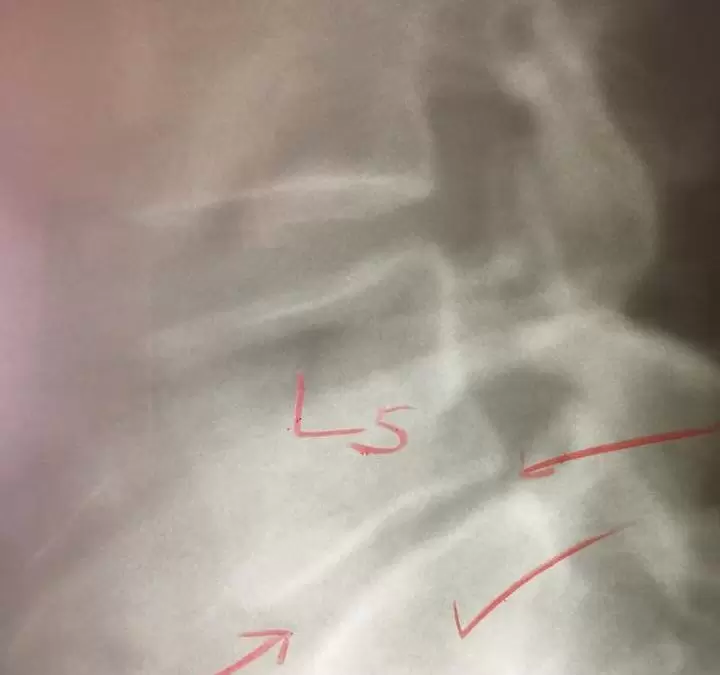

After 2 years of #Chiropractic corrective care we have been able to regenerate Isabellas degenerative L5 intervertebral disc disease. The human body can overcome extreme health obstacles if you just remove the interference and put the necessary time in.